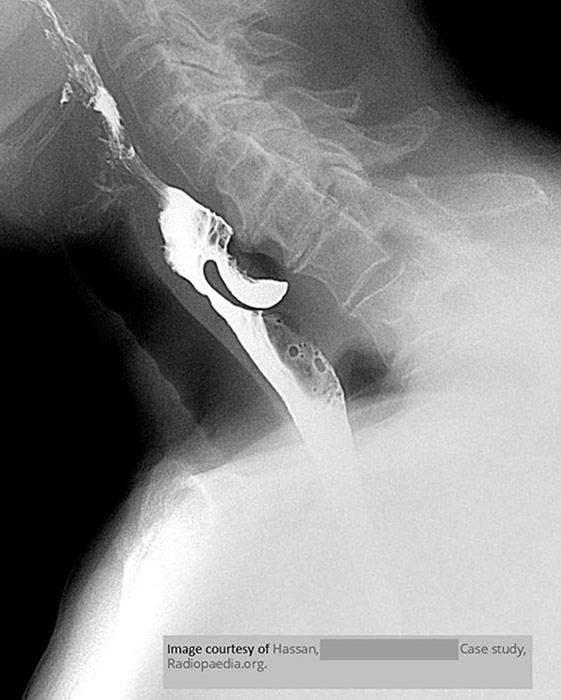

What is the gold-standard imaging study for Zenker’s diverticulum?

Barium swallow.

What is the typical radiographic appearance of Zenker’s diverticulum?

Posterior outpouching at the pharyngoesophageal junction.